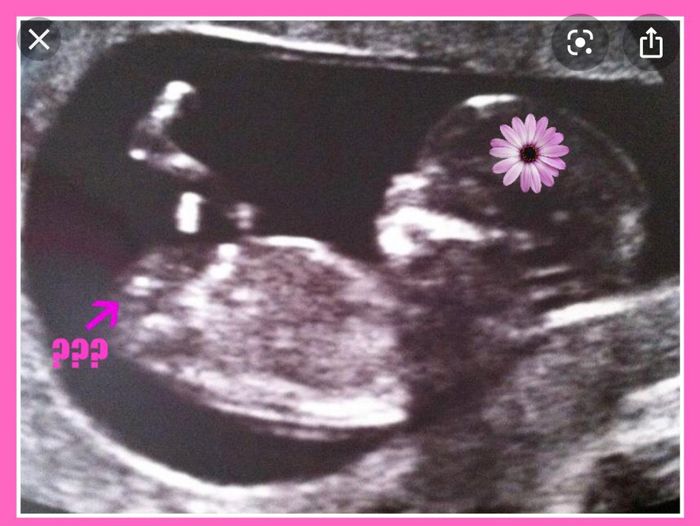

Ecografia di stamattina. Sono a 10+6. Che ne pensate? Maschio o femmina? I primi di maggio farò il prelievo per il dna fetale.